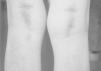

Escorbuto: una causa inusual de púrpura, equimosis y artralgias

Scurvy: an unusual cause of purpura, ecchymosis and arthralgias